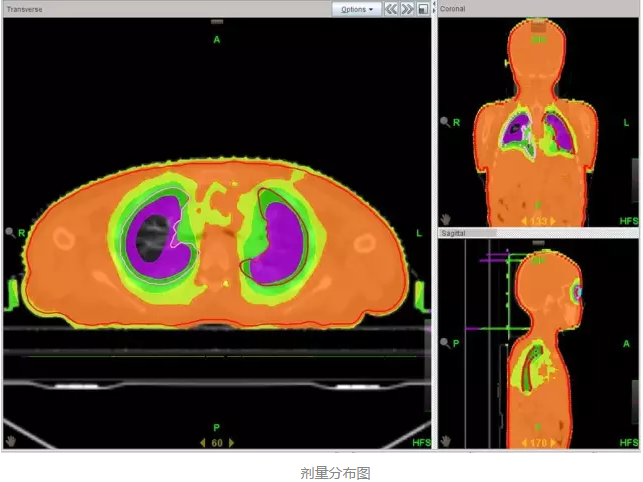

еңЁе®һйӘҢйғ‘еӨ§дёҖйҷ„йҷўйҰ–дҫӢ TBI зҡ„еҺҶзЁӢдёӯ����пјҢж”ҫе°„жІ»з–—йғЁжқҺеӣҪж–Үдё»д»»и®Өзңҹ TBI зҡ„ж•ҙдёӘжүӢиүәжөҒзЁӢ����пјҢйғӯи·ғдҝЎеүҜдё»д»»иҜҰз»Ҷи®Өзңҹе®һйӘҢдёҺеҢ…з®Ў����пјҢеҢ»з”ҹз»„еј ж—ӯдёңеҢ»з”ҹйҳ…иҜ»зӣёе…іж–ҮзҢ®����пјҢ并дәІиҮӘеҲ°ејҖеұ•иҜҘжүӢиүәйўҶе…Ҳзҡ„е№ҝе·һеҶӣеҢәжҖ»еҢ»йҷўж”ҫ疗科еӯҰд№ ����пјҢиҜҘйҷўж”ҫ疗科й»Һйқҷдё»д»»зҡ„ж”ҫз–—еӣўйҳҹз»ҷдәҲдәҶж— з§Ғзҡ„йјҺеҠӣеӨ§дёҫиө„еҠ©���пјӣзү©зҗҶз»„з»„й•ҝ马йҳіе…үеҗ‘еҜјзү©зҗҶз»„е…ЁдҪ“иҒҢе‘ҳиө·еҠІеҚҸи°ғ����пјҢзҺӢжө·жҙӢзү©зҗҶеёҲдҪҝз”Ёе‘ЁеӨ©дј‘жҒҜзҡ„ж—¶й—ҙдёҫиЎҢиҙЁйҮҸжҺ§еҲ¶жқҘзЎ®���пјӣйўҠе’§зҳҹзІ•зі»йӮЈеҜ°���пјӣжүӢиүәз»„з»„й•ҝжӣ№дҝҠеҚҺеҗ‘еҜјжүӢиүәз»„е…ЁдҪ“жҲҗе‘ҳж”»еқҡе…Ӣйҡҫ����пјҢжңҖз»ҲеңЁеҗ„дёӘйғЁеҲҶзҡ„й…ҚеҗҲиө·еҠІдёӢ����пјҢ2016 е№ҙ 5 жңҲ 16 ж—Ҙйғ‘е·һеӨ§еӯҰ第дёҖйҡ¶еұһеҢ»йҷўйҰ–дҫӢ TBI жІ»з–—е®ҢжҲҗ����пјҢз”ұдәҺж”ҫе°„жІ»з–—йғЁдҪҝз”Ё TOMO HD еҠ йҖҹеҷЁе®һйӘҢзҡ„ TBI ����пјҢеүӮйҮҸжј«иЎҚеҚҒеҲҶе®Ңе–„пјҲеҰӮдёӢеӣҫжүҖзӨәпјү����пјҢзұ»дјјй•ҢеҲ»����пјҢд»ҘжҳҜеҸҲиў«з§°дёәгҖҢй•ҢеҲ»ејҸе…Ёиә«ж”ҫз–—гҖҚ����гҖӮ